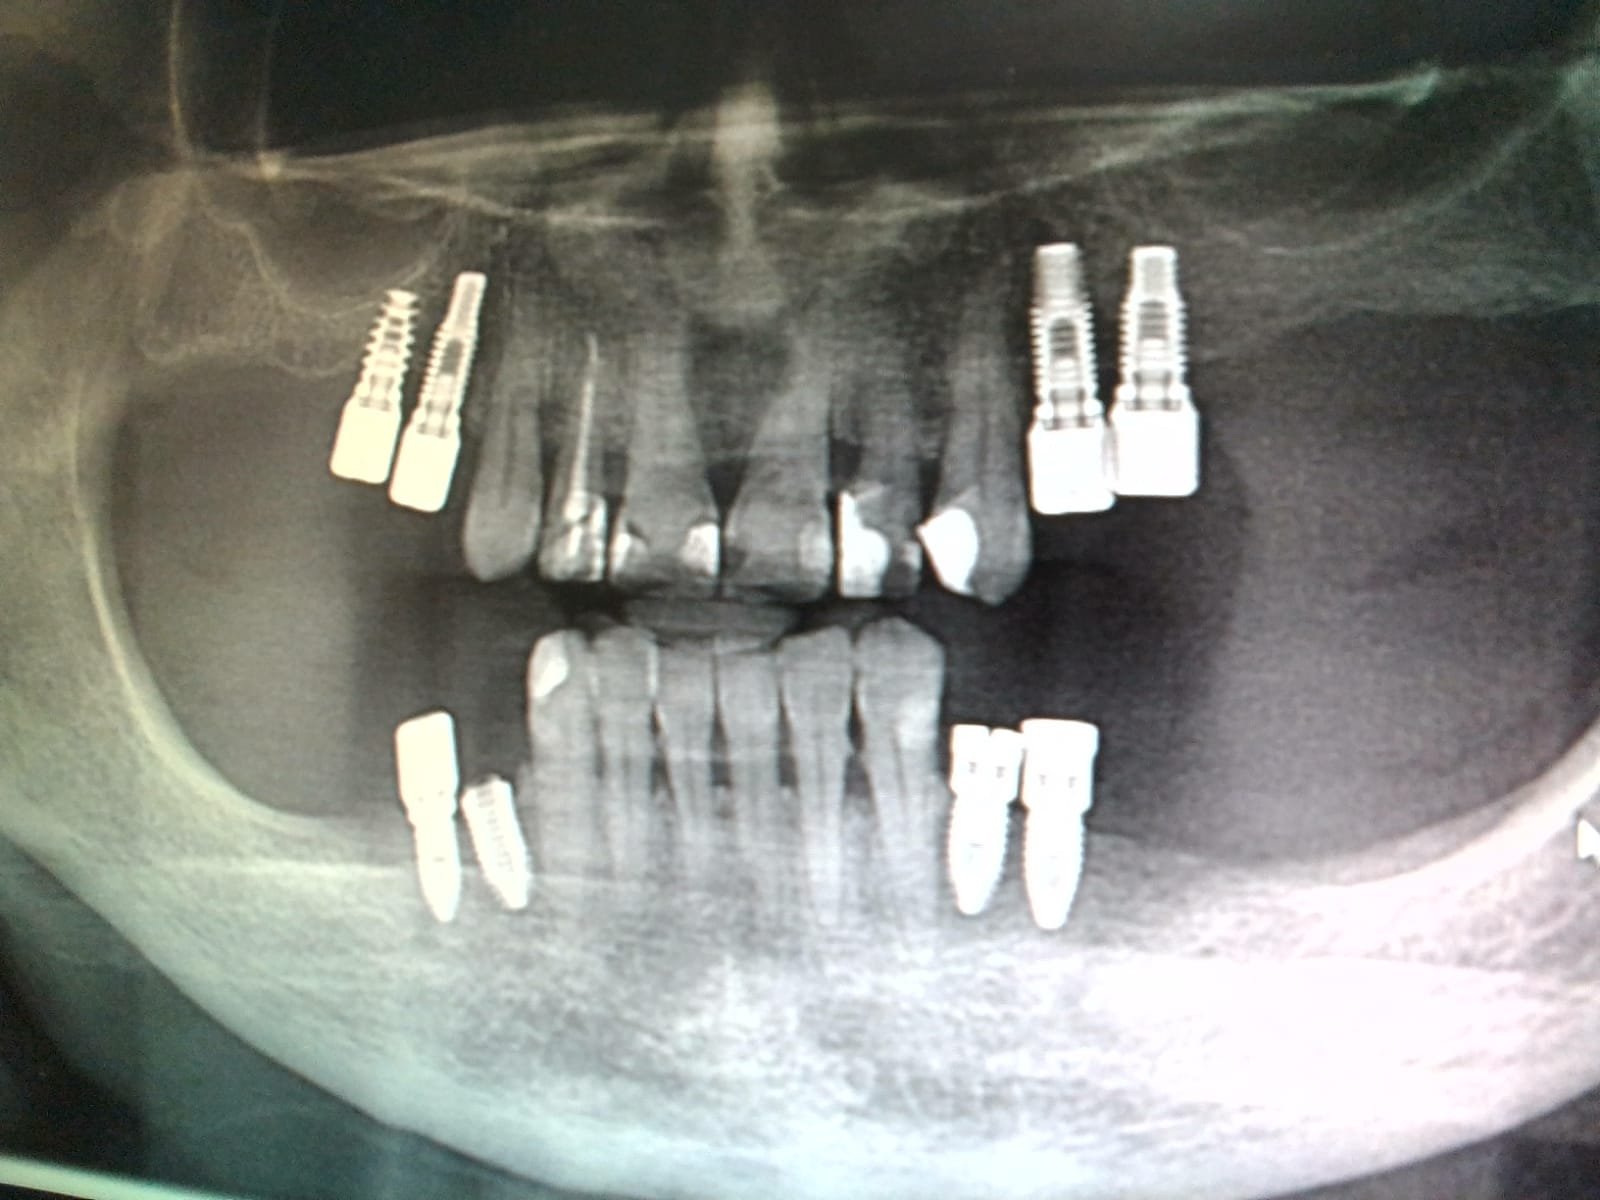

Hola: esto es un nuevo caso idental. Necesito saber el tipo de implantes del maxilar superior e inferior izquierdo. Muchísimas gracias